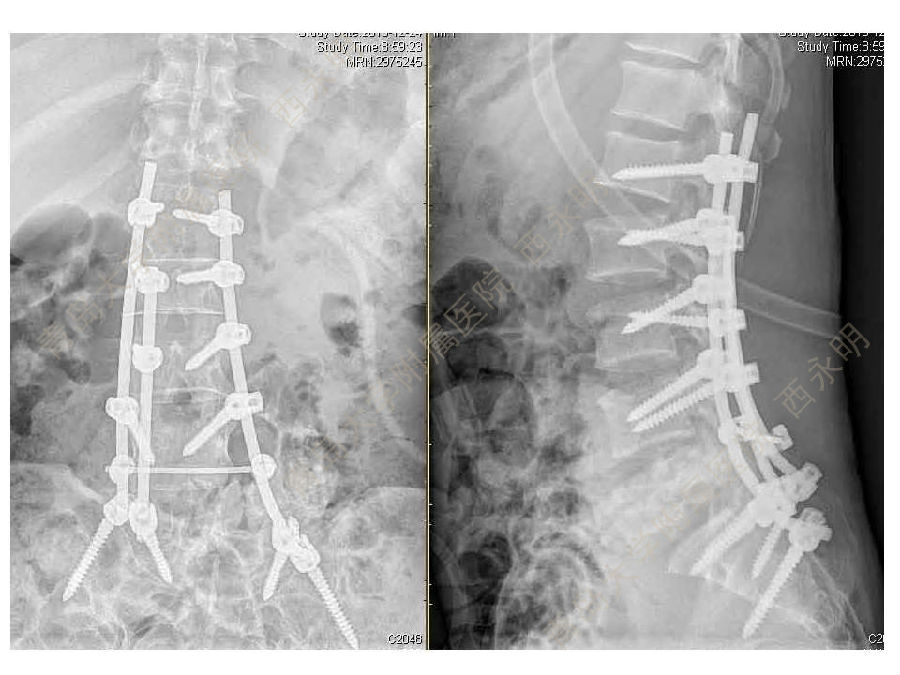

皮质骨螺钉技术及临床应用

颈椎伤病、脊柱畸形和脊柱肿瘤以及颈胸腰椎退变性疾病的微创治疗。长期从事临床一线的医、教、研工作,在多年的临床实践中积累了丰富的经验,并形成了以脊柱外科为专业方向,以颈椎外科、脊柱畸形和脊柱肿瘤为专业特色。